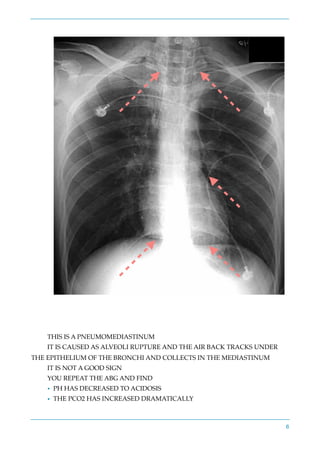

THIS IS A PNEUMOMEDIASTINUM

IT IS CAUSED AS ALVEOLI RUPTURE AND THE AIR BACK TRACKS UNDER

THE EPITHELIUM OF THE BRONCHI AND COLLECTS IN THE MEDIASTINUM

IT IS NOT A GOOD SIGN

YOU REPEAT THE ABG AND FIND

• PH HAS DECREASED TO ACIDOSIS

• THE PCO2 HAS INCREASED DRAMATICALLY